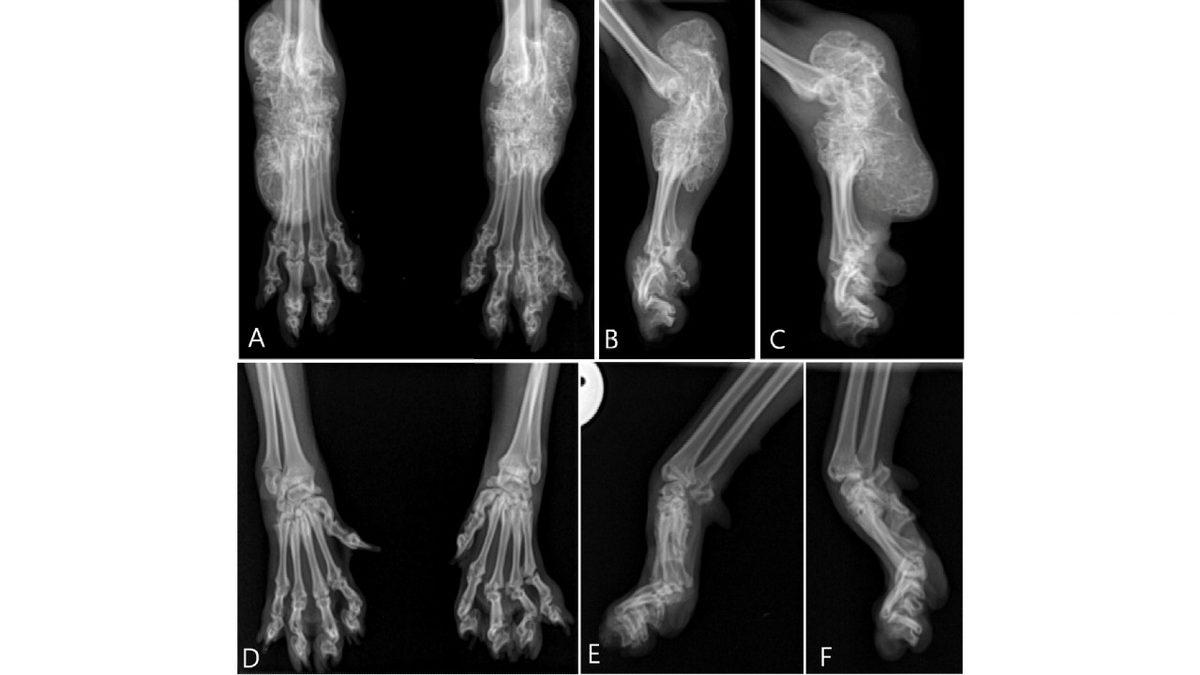

Scottish Fold'ların ve British'lerin sakin görüntülerinin altında eklem ağrıları yatıyor.

En belirgin özellikleri katlanmış kulakları olan Scottish Fold’lar, dışarıdan tatlı görünseler de bu özellikleri genetik bir mutasyon sonucu ortaya çıkar ve birçok sağlık sorununa yol açar.

Bu kedilerin kulaklarındaki katlanma, kıkırdak dokusundaki mutasyon sonucu oluşur ve kıkırdak yapısındaki sorunlara, artrite, kulak enfeksiyonlarına, ortopedik sorunlara, omurga ve iç kulak problemlerine neden olur. Sessiz, sakin olmalarının altında yatan sebep de bu fiziksel problemlerdir. Siz fark etmeseniz de sürekli olarak ağrı hissederler.

Tatlı kedi videolarında görmeye alışık olduğumuz Munchkin'lerin bacakları onları sevimli gösterse de yapıları nedeniyle acıya yol açıyor.

İnsanlar tarafından yapay olarak üretilen Munchkin’lerin “sevimli olmaları için” kısa bacaklı ve uzun gövdeli gen mutasyonuyla üretilirler. Kısa bacakları yüzünden omurga yapıları etkilenir ve sürekli olarak bel, sırt, kalça omurga ağrısı çekerler.

Kemik ve eklem sağlıkları bozulur, artrit gibi sorunlar ortaya çıkar. Üstelik vücutları yüzünden farklı bir yürüme stiline sahip oldukları için zamanla eklem ve kas sorunları oluşur.

Sosis köpek de dediğimiz Dachshund'lar, epilepsi dahil çokça hastalığa yatkın.

Kısa bacakları ve uzun vücutlarıyla ön plana çıkan Dachshund’lar, genetikleri nedeniyle birçok ortopedik soruna yatkınlardır. Kalça eklemi gelişimindeki anormallikler yüzünden ağrı ve hareket kısıtlanması ortaya çıkar.